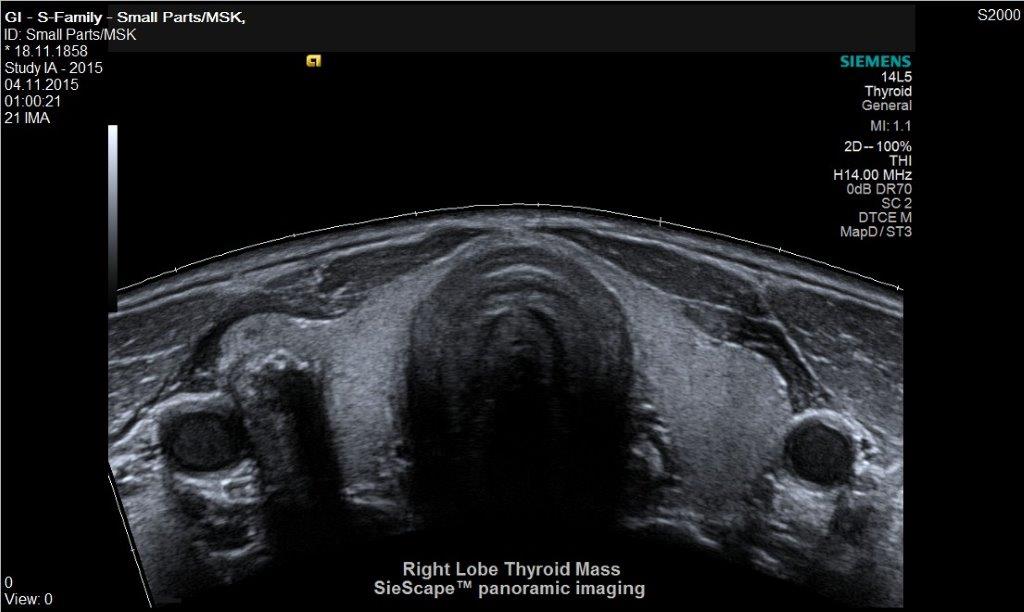

• Schilddrüse